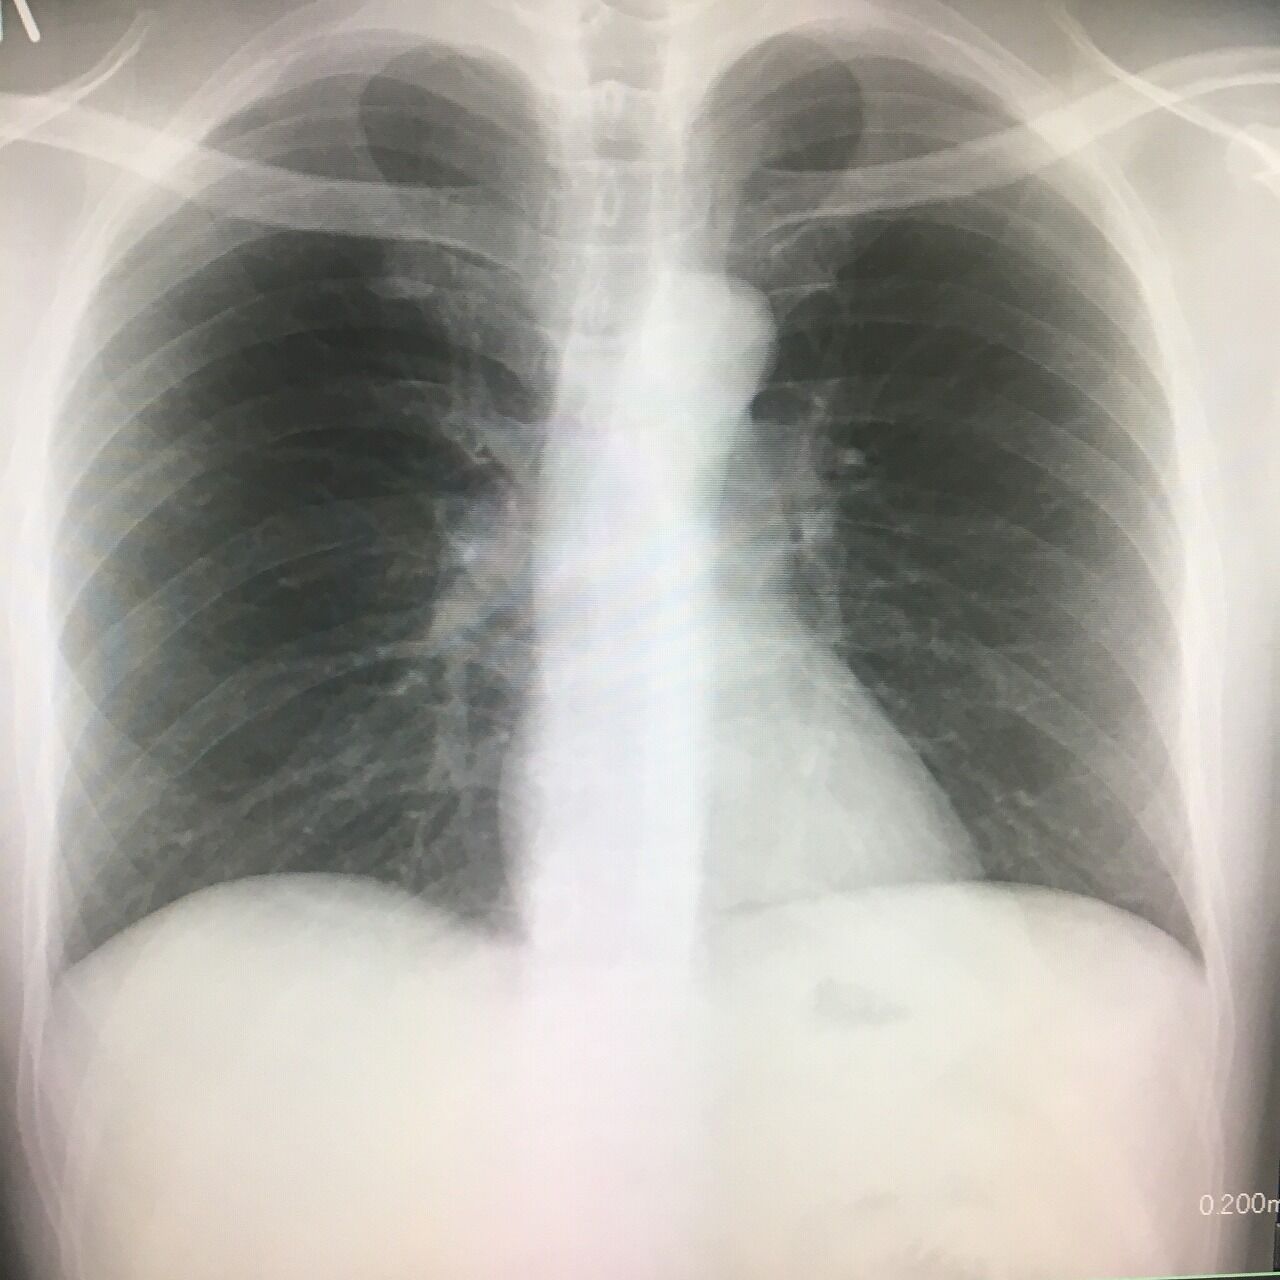

健康診断のレントゲン。心臓が、意外と真ん中にあることに驚く。もっと、左胸だと思ってた。